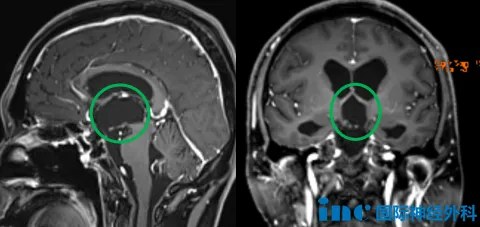

江先生的手术最终获得十分满意的切除,而且恢复良好,术后正有序地进行激素替代治疗。术后1个多月随访时,江先生术前行走不稳、反应略迟钝、记忆力下降等症状得到明显改善,整体恢复良好,江先生已经可以正常行走,但还稍有些乏力,存在部分记忆混乱等症状。

然而,到了术后2个月福教授再次随访时,江先生精神良好,他笑着告诉福教授:“现在挺好的,一切都好,所以非常感谢福教授!”此时,乏力和记忆混乱的问题也基本恢复,福教授详细询问了江先生目前的服药情况和具体剂量,并给出了相应的调整建议。